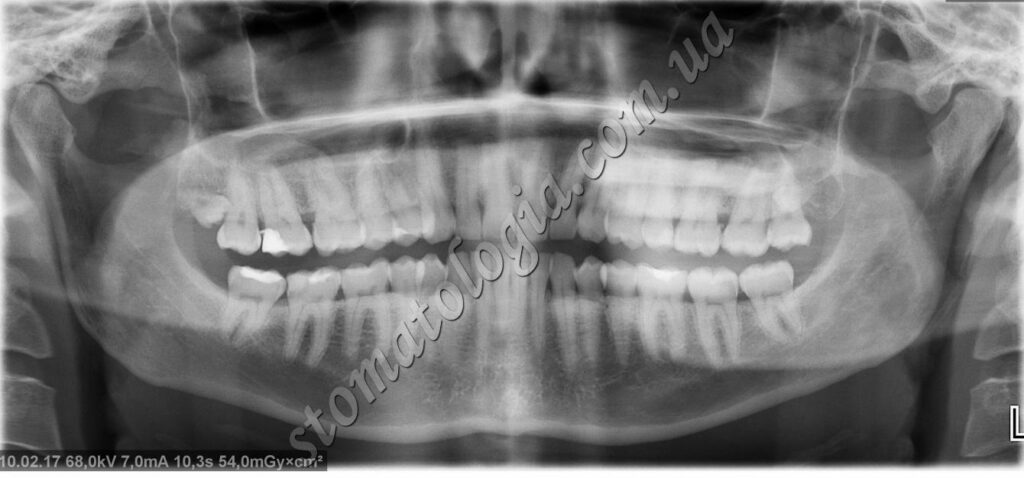

Ретиновані зуби: усі зуби мудрості (4 зуба) та ікла верхньої щелепи. Ретиновані й дистоповані зуби часто не можна побачити під час візуального огляду, але їх добре видно на КТ і рентгені